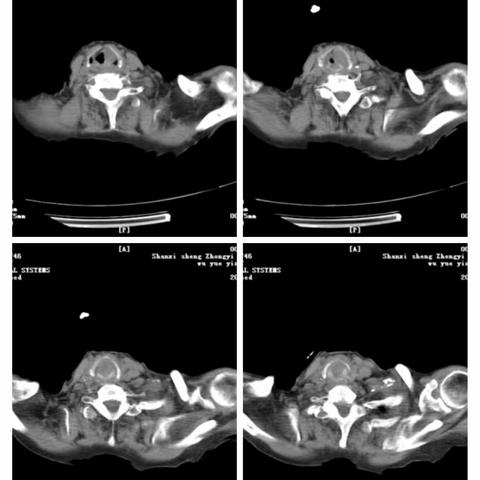

主动脉弓旁小细胞肺癌粒子植入术后纵隔血肿